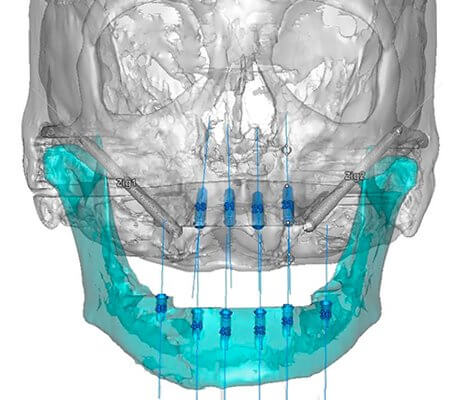

La cirugía oral guiada (COG) es una técnica innovadora que utiliza tecnología de imagen digital 3D, como la tomografía computarizada (TC) o el escáner CBCT, para planificar y realizar procedimientos quirúrgicos orales con mayor precisión y seguridad. A través de un software especializado, se crea un modelo tridimensional virtual de la boca del paciente, permitiendo al cirujano visualizar con exactitud la anatomía ósea, la posición de los dientes, los nervios y otras estructuras importantes. Este plan virtual se traduce luego en una guía quirúrgica física, normalmente hecha de plástico, que se utiliza durante la cirugía para guiar la colocación precisa de implantes dentales, extracciones complejas o cualquier otra intervención quirúrgica oral. En esencia, la COG minimiza la invasión, reduce el tiempo de cirugía y maximiza la precisión del procedimiento, resultando en una recuperación más rápida y confortable para el paciente.

La planificación preoperatoria es un paso crucial en la COG. Comienza con la obtención de un escáner CBCT o TC de alta resolución de la boca del paciente. Esta imagen 3D se importa luego a un software especializado de planificación quirúrgica, donde el cirujano analiza la anatomía ósea, la posición de los dientes, los nervios y otras estructuras importantes. Basándose en este análisis, el cirujano diseña el plan quirúrgico virtual, determinando la posición ideal para los implantes, el tamaño y el tipo de implante necesario, y la trayectoria óptima de la fresa quirúrgica. Este plan se utiliza luego para fabricar una guía quirúrgica personalizada que se utilizará durante la cirugía para guiar la colocación precisa de los implantes.

- Obtención de imágenes 3D: Se realiza un escáner CBCT o TC de alta resolución.

- Análisis de la imagen: El cirujano analiza la anatomía ósea y las estructuras circundantes.

- Diseño del plan quirúrgico virtual: Se determina la posición, tamaño y trayectoria de los implantes.

Materiales y Tecnología Utilizada en Cirugía Oral Guiada

La COG se basa en el uso de tecnología avanzada de imagen y software especializado. El escáner CBCT o TC proporciona imágenes tridimensionales de alta resolución de la boca del paciente. Existen diferentes softwares de planificación quirúrgica, cada uno con sus propias características y funcionalidades, que permiten al cirujano diseñar el plan quirúrgico virtual y generar la guía quirúrgica. La guía quirúrgica misma, normalmente fabricada con plástico de alta precisión, actúa como una plantilla que guía la fresa quirúrgica durante la cirugía, asegurando la precisión y la seguridad del procedimiento. Además, se utilizan instrumentos quirúrgicos específicos diseñados para trabajar con la guía.

- Escáner CBCT o TC: Para obtener imágenes 3D de alta resolución.

- Software de planificación: Para diseñar el plan quirúrgico virtual y generar la guía quirúrgica.

- Guía quirúrgica: Una plantilla de plástico que guía la fresa quirúrgica durante la cirugía.

Una guía quirúrgica dental es un dispositivo de precisión, generalmente fabricado con materiales como el titanio o la resina, que se utiliza para planificar y realizar procedimientos quirúrgicos orales con mayor precisión y seguridad. Se diseña individualmente para cada paciente basándose en imágenes de diagnóstico por imagen, como CBCT (tomografía computarizada de haz cónico), y sirve como una plantilla que guía al cirujano durante la colocación de implantes dentales, injertos óseos, o cualquier otro procedimiento quirúrgico complejo en la boca. Su objetivo principal es minimizar la invasión quirúrgica, reducir el tiempo de operación, mejorar la precisión de la colocación de los implantes o injertos y, en consecuencia, maximizar las posibilidades de éxito del tratamiento. Se utilizan para asegurar la posición, la profundidad y el ángulo correctos de los implantes, minimizando el riesgo de daño a estructuras anatómicas importantes como nervios o senos maxilares.

Proceso de Fabricación de una Guía Quirúrgica Dental

- Obtención de imágenes CBCT: Se realiza un escáner CBCT del paciente para obtener imágenes tridimensionales de la anatomía oral.

- Planificación virtual: El software de planificación CAD/CAM permite al cirujano diseñar la posición ideal de los implantes y la guía quirúrgica.

- Fabricación de la guía: La guía se fabrica a través de técnicas de fresado o impresión 3D, utilizando materiales biocompatibles.